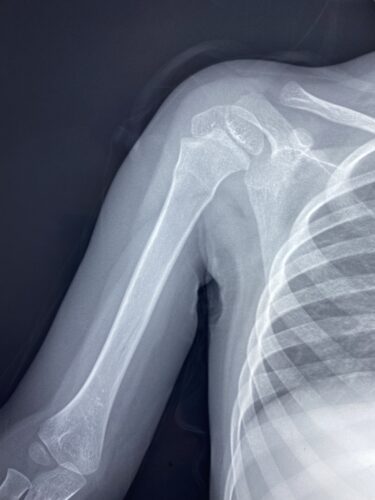

さわやか千葉県民プラザ(肩関節脱臼)

さわやか千葉県民プラザ(上腕骨外科頸骨折)

さわやか千葉県民プラザ(上腕骨外科系骨折)

小児上腕骨外顆回転骨折の1症例について

肘関節前方脱臼の1症例について